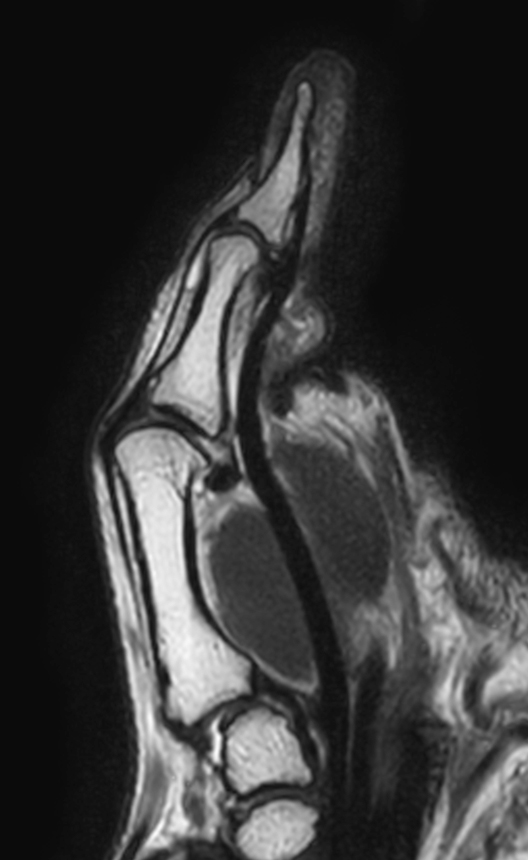

Patient with pathology on the thumb. ExamCard includes mDIXON XD TSE to achieve uniform, complete and consistent fat-free imaging. It simplifies the scan procedure by providing multiple image types in one single scan, including with/without fat suppression contrasts.

PDw TSE mDIXON XD (In Phase)